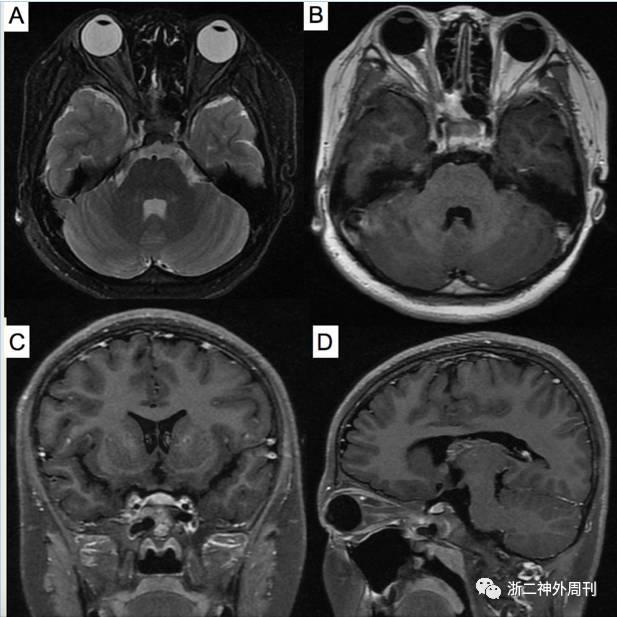

协和医院最终出院诊断为头痛原因不明,中小血管炎可能。予美卓乐4mg qd,后加用甲氨蝶呤 4片 qw口服治疗。1年后患者复查头颅MRI示右侧眶尖-海绵窦病变较前缩小缓解(图3)。目前仍在继续随访中。

图3. 术后1年复查头颅MRI:A)T2加权像轴位、B)增强后轴位、C)冠状位和D)矢状位示见右眼眶尖部-海绵窦病变较术前缩小缓解。